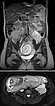

Coronal (top) and axial (bottom) T2-weighted, fat-suppressed MR sequences without contrast at baseline before pregnancy.